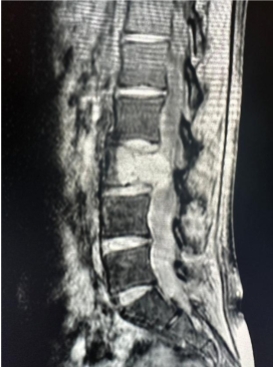

Common diagnostic tests include:

- X-rays (to assess spinal alignment and bending points)

- CT scans (for bony structures and abnormalities)

- MRI scans (to examine nerve and soft tissue damage)

- Blood tests (to check for neurological or autoimmune disorders such as Parkinson's disease)

Because DHS can mimic other diseases, an experienced specialist is necessary for an accurate diagnosis.